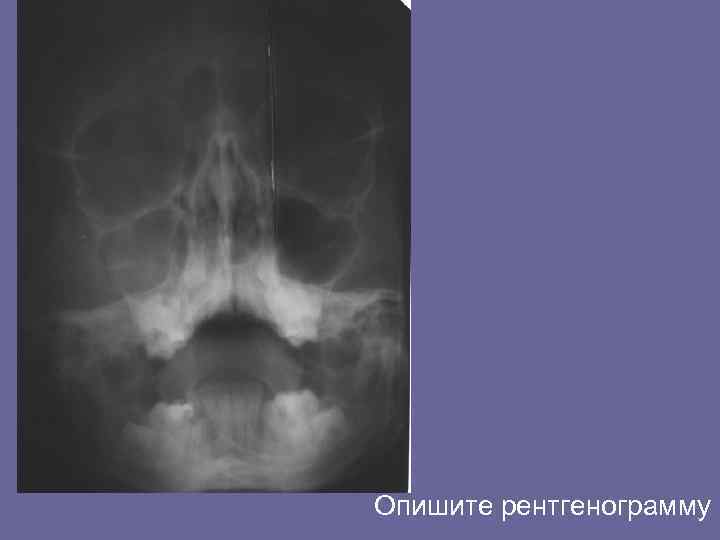

Опишите рентгенограмму

По мере рост кисты могут распространяться одновременно в сторону полости носа и в сторону верхнечелюстной пазухи